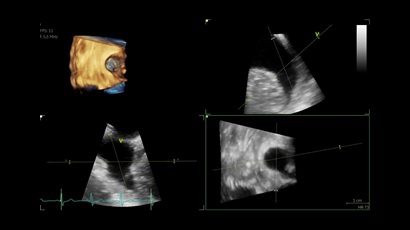

GE VIVID IQ - это передовая портативная система ультразвуковой диагностики, специально разработанная для обеспечения высокого качества образов и мобильности. Благодаря своим компактным размерам и легкому весу, VIVID IQ легко переносится и позволяет проводить УЗИ исследования в различных местах, включая комнаты пациентов, отделения скорой помощи и операционные.

GE VIVID IQ – это ультрасовременный, выполненный в виде ноутбука УЗИ сканер с самым передовым техническим оснащением для проведения диагностических обследований сердечно-сосудистой системы человека. Его особенно оценят бригады скорой помощи из-за малого веса всего 4,5 кг., удобства переноски, а также быстрого выхода из состояния сна для начала работ.

• Vivid IQ 4D с поддержкой технологии объемной реконструкции

• Передовые технологии, такие как 4D чреспищеводная эхокардиография, ЭКГ, стресс-эхо, внутрисердечная ультразвуковая эхокардиография, тканевый доплер и другие.